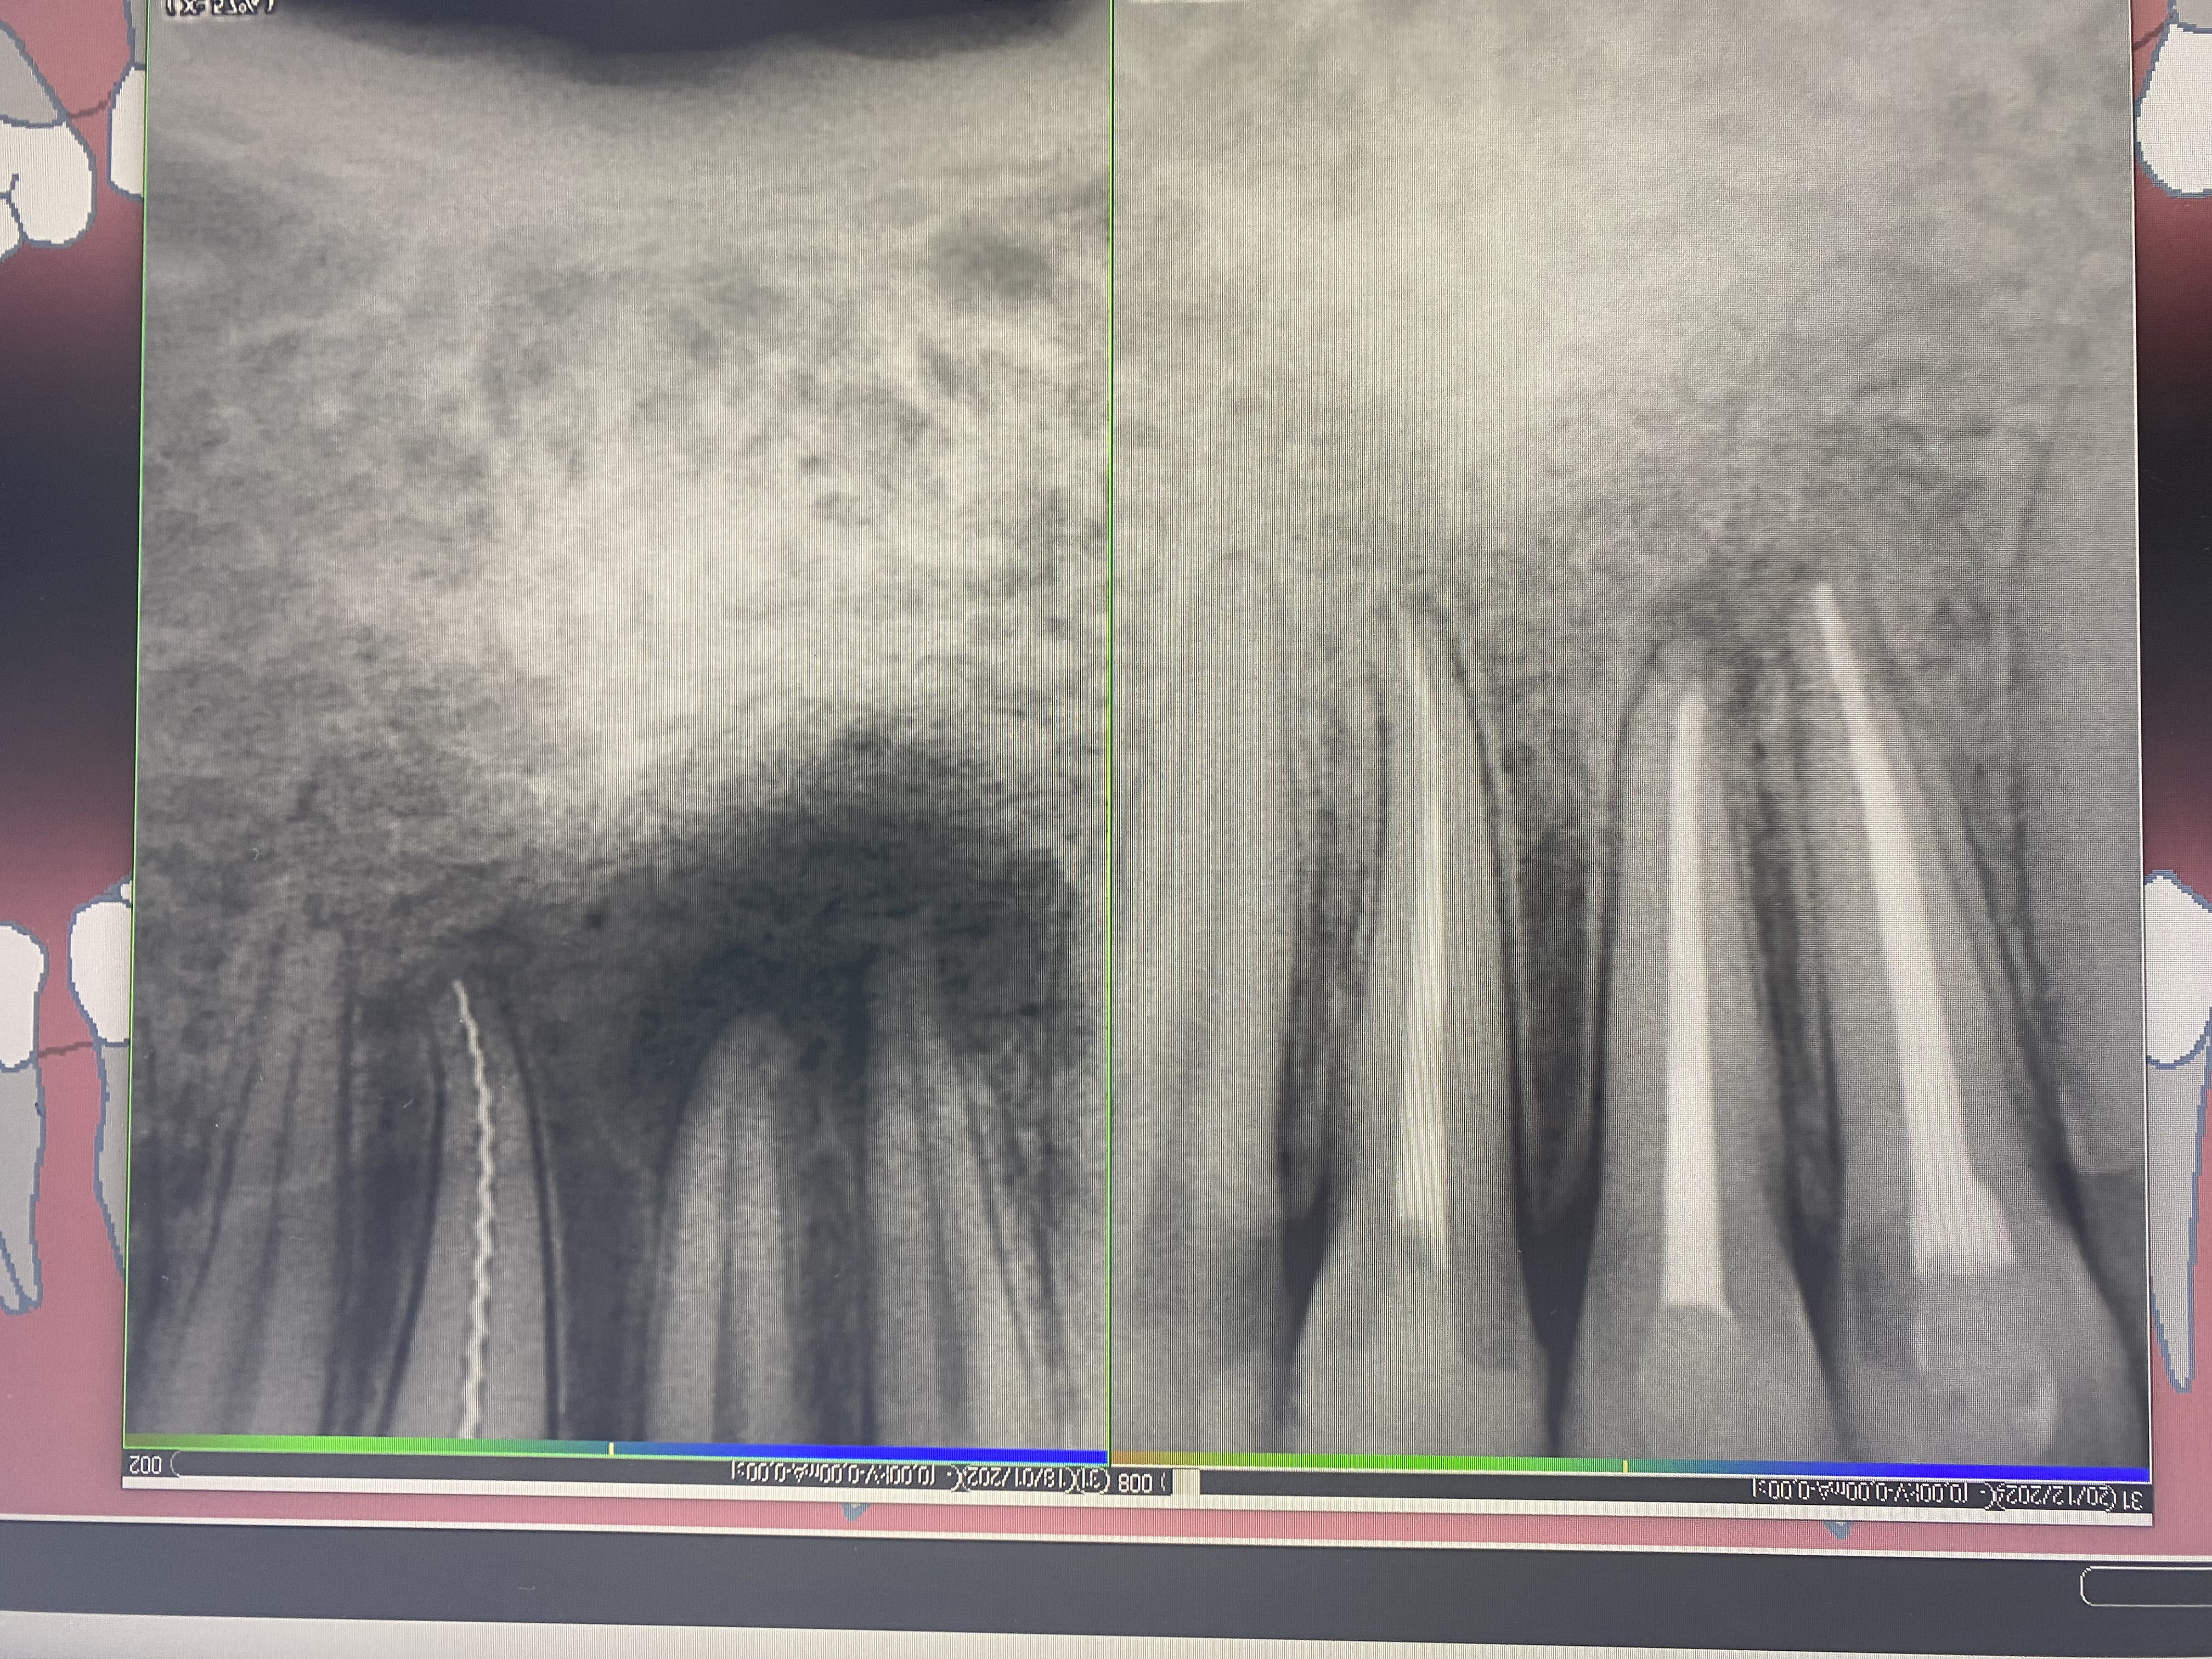

- Владение современными методиками пломбирования корневых каналов, обработки и распломбировки многокорневых зубов любой степени сложности

- Проведение полной профессиональной консультации по здоровью зубочелюстной системы, составление комплексного плана лечения, рекомендации по поддержанию качественной гигиены полости рта, обучение правильной технике чистки зубов, анализ снимков на визиографе и рентген-аппарате, анализ Клкт снимков